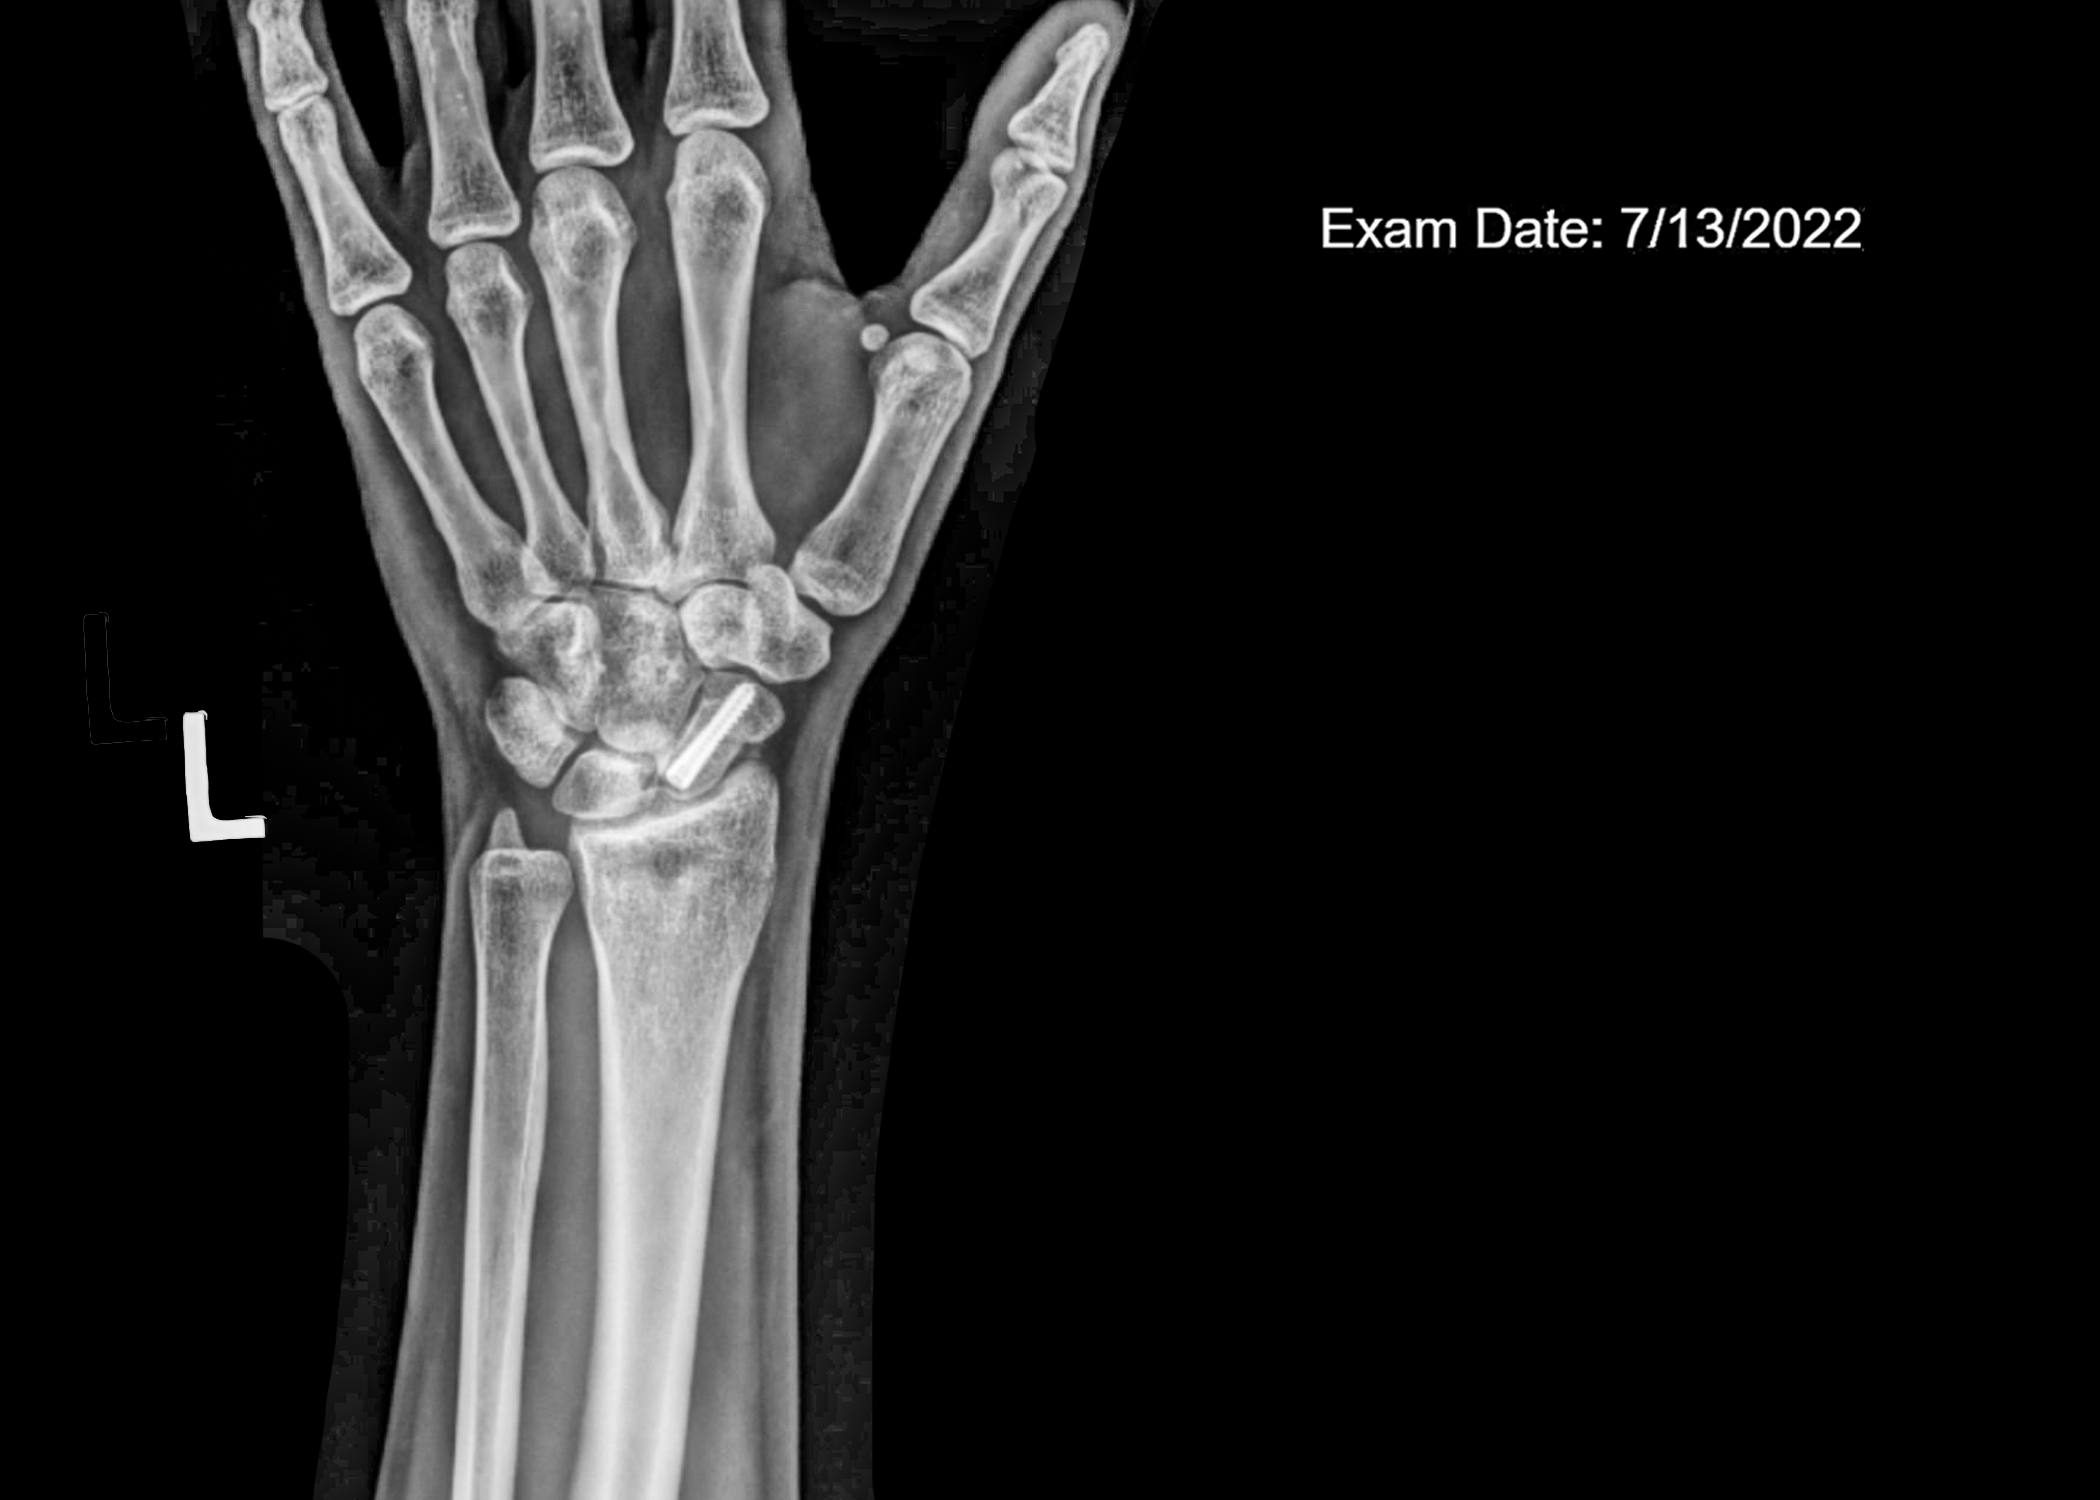

faux flowers X-rays, and tape installation

“Those sounded like terrible memories to have. I wonder if they will ever come back. I hope they don’t” -6/14/2022. Although my memories from the fall never came to me, the aftermath can never be forgotten. More than anything, I wanted to find meaning in my accident.